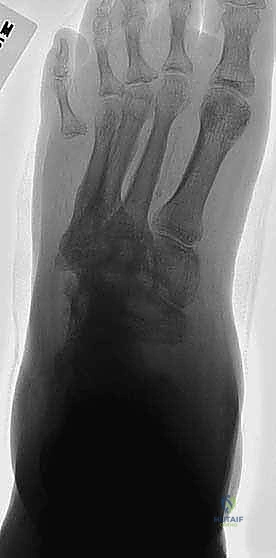

- الانهيار الهيكلي: تنهار عظام منتصف القدم، مما يؤدي إلى سقوط قوس القدم الطبيعي وتحول أسفل القدم إلى شكل محدب يشبه "الكرسي الهزاز" (Rocker-bottom deformity).

- التشوه البصري: تغير في شكل القدم، ظهور بروزات عظمية في باطن القدم، أو انحراف الكاحل.

الخطر الأكبر: التقرحات، التهاب العظام، وشبح البتر

لماذا نعتبر تصحيح تشوهات شاركو أمراً حتمياً في بعض الحالات؟ الإجابة تكمن في "البروزات العظمية". عندما تنهار عظام منتصف القدم نحو الأسفل، فإنها تضغط بشدة على الجلد من الداخل أثناء المشي.